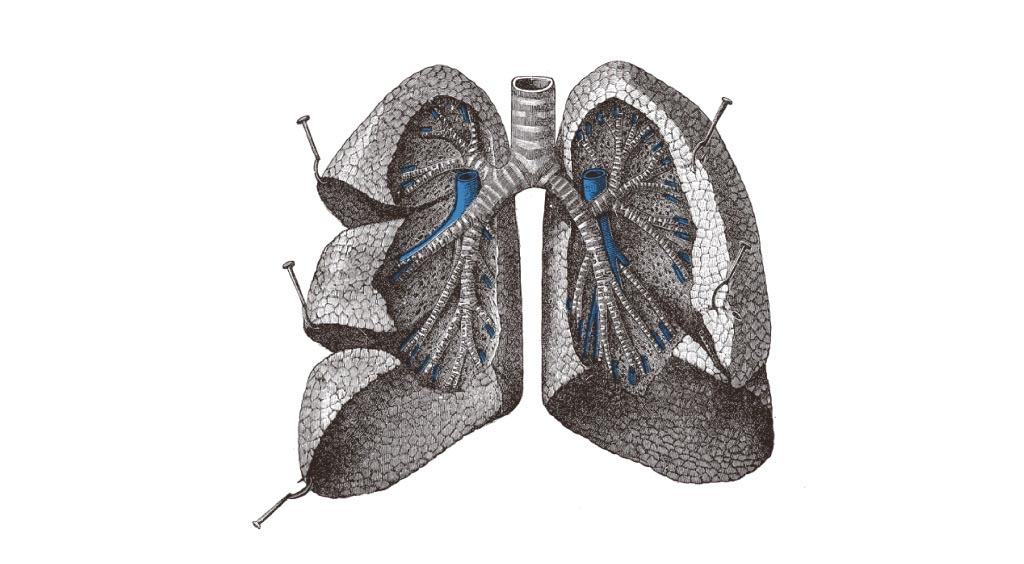

気管は第6頸椎の高さで、喉頭の輪状軟骨の下から垂直に下降する長さ10~13cmで直径が約2cmの管である。前頸部では体表から気管を触れることができる。気管の壁は約20個の馬蹄形の気管軟骨が積み重なってできている。軟骨を欠く後壁は膜性壁といい、平滑筋と粘膜だけになる。気管は胸腔に入ると心臓の上後方(第5胸椎の高さ)で左右の気管支に分かれる。右気管支は太くて短く、垂直に近く傾斜する。左気管支は細くて長く、水平に近い傾斜を持つ。このように左右の気管支の太さ・長さ・走行に違いがあるので、誤って気管支に吸い込んだ異物は右気管支に、さらには右肺に入りやすい。(p.65 気管と気管支)

気管支は肺門から肺に入ると、まず各肺葉にいく葉気管支に分かれる。右肺では上葉気管支・中葉気管支・下葉気管支の3本に、左肺では上葉気管支・下葉気管支の2本に分かれる。このあと各葉気管支は2~4本の区域気管支に分かれる。区域気管支が支配する領域を肺区域というが、肺区域は右肺では10個、左肺では9個ある。肺区域はそれぞれ重なり合うことがなく、分布する血管もそれぞれ独立している。そのため肺がんなどで肺組織を切除する場合は、肺区域を単位とした区域切除術などが行われる。

区域気管支は区域内で分岐して気管支枝となり、最後に軟骨を失って細気管支となる。細気管支は各肺小葉に入り、分岐して終末細気管支となる。細気管支は肺小葉への空気の流入を調節する。端息発作は平滑筋の病的なけいれんに伴う細気管支の過度の収縮によるという。終末細気管支は呼吸細気管支に続く。その壁の一部には肺胞が付いて、さらにその数が増えて肺胞管・肺胞嚢となる。(p.66 肺区域)